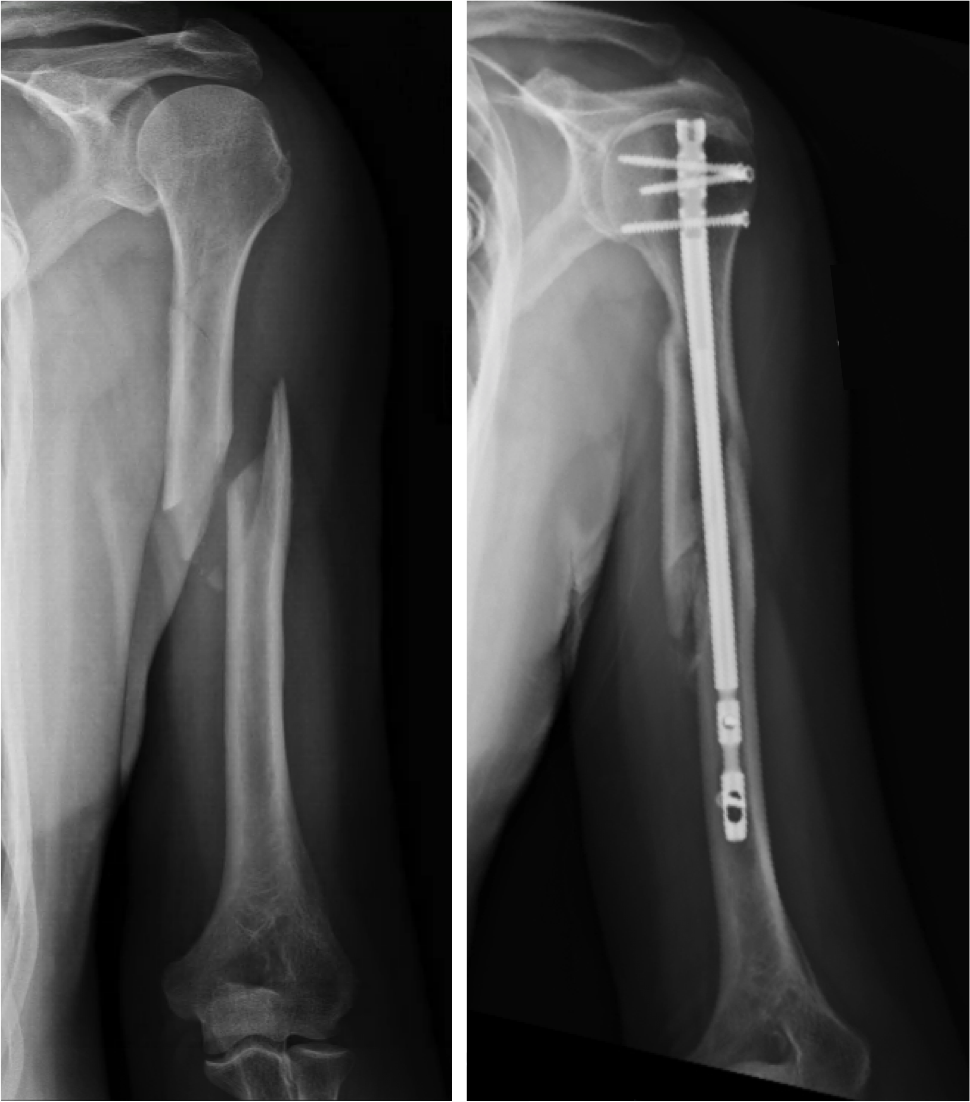

Pathological humeral shaft fracture in unicameral bone cyst Image What Is A Humeral Neck Fracture A proximal humerus fracture is when the top part of the upper arm is broken. The humerus is the long bone in your upper arm. This activity illustrates the evaluation and treatment of proximal humerus fractures and reviews the role of the interprofessional team in managing those with this. A humerus fracture is the medical name for breaking the bone. What Is A Humeral Neck Fracture.

Figure 6 from Locking intramedullary nails and locking plates in the What Is A Humeral Neck Fracture In most cases these fractures can be treated without surgery. What is a proximal humerus fracture? A proximal humerus fracture is when the top part of the upper arm is broken. A humerus fracture is the medical name for breaking the bone in your upper arm (your humerus). The neck of the humerus. This type of fracture or break is. What Is A Humeral Neck Fracture.

Humeral shaft fractures Management of complications What Is A Humeral Neck Fracture The humerus is the long bone in your upper arm. A humerus fracture is the medical name for breaking the bone in your upper arm (your humerus). In most cases these fractures can be treated without surgery. The humerus is the bone at the top of the arm which fits into the socket of the shoulder to form the shoulder. What Is A Humeral Neck Fracture.

Humeral Shaft Fractures What Is A Humeral Neck Fracture This activity illustrates the evaluation and treatment of proximal humerus fractures and reviews the role of the interprofessional team in managing those with this. The neck of the humerus. A proximal humerus fracture is when the top part of the upper arm is broken. The humerus is the bone at the top of the arm which fits into the socket. What Is A Humeral Neck Fracture.